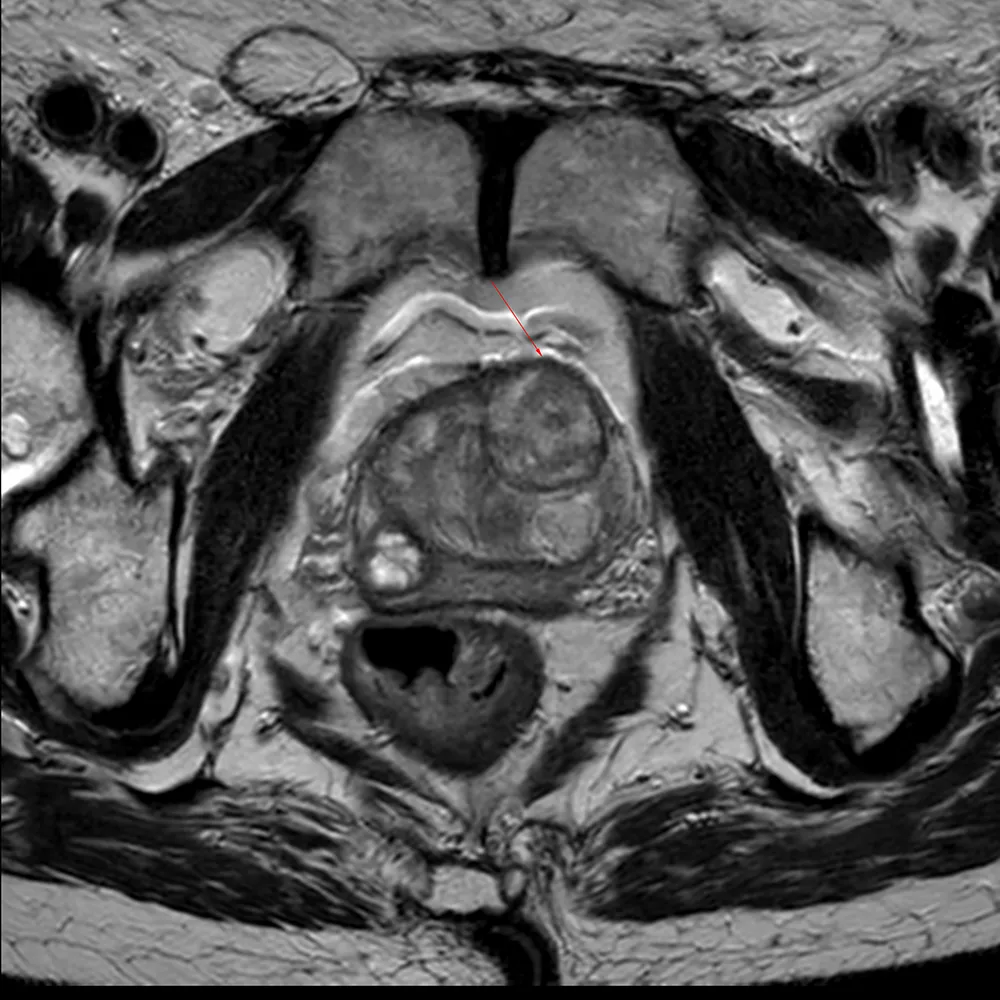

Das Prostata-MRT ist eine spezielle Form der Magnetresonanztomographie, bei der hochauflösende Bilder der Prostata und des angrenzenden Gewebes erstellt werden. Es handelt sich um eine nicht invasive Methode, die ohne den Einsatz von Röntgenstrahlen auskommt. Im Vergleich zu anderen bildgebenden Verfahren, wie der transrektalen Ultraschalluntersuchung oder der Prostatabiopsie, bietet das Prostata-MRT eine exzellente Bildqualität und eine besonders präzise Darstellung der Gewebestruktur.

Das Prostata-MRT liefert wichtige Informationen, die es ermöglichen, sowohl Tumore als auch andere pathologische Veränderungen im Gewebe frühzeitig zu erkennen. Gerade in den Anfangsstadien von Prostatakrebs, in denen noch keine Symptome auftreten, kann das MRT potenziell auffällige Stellen sichtbar machen, die ansonsten unentdeckt bleiben würden.

Früherkennung von Prostatakrebs: Das Prostata-MRT ist eines der präzisesten Verfahren zur Erkennung von Tumoren in der Prostata. In den frühen Stadien, in denen der Tumor möglicherweise noch keine Symptome verursacht, können mit dem MRT selbst kleinste Veränderungen im Gewebe entdeckt werden. Eine frühzeitige Diagnose ermöglicht eine gezielte Behandlung, bevor sich der Tumor ausbreitet.